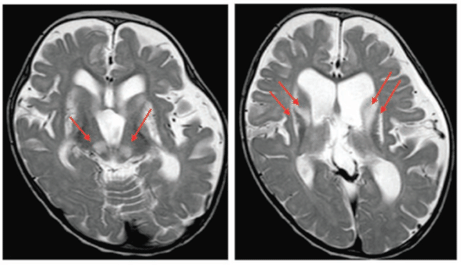

PTCD3異常症は、子宮内発育遅延、発達遅滞、ミオクローヌス、ミトコンドリア脳症などを呈す疾患です。頭部MRI画像診断では、大脳基底核や脳幹で両側対称性白質病変を示しており、これは典型的なLeigh脳症と一致していました(図1)。患者由来線維芽細胞を用いたミトコンドリア呼吸鎖複合体活性診断では、呼吸鎖ⅠとⅣの低下を示していました。

図1.大脳基底核、脳幹の両側対称性白質病変(T2強調画像)